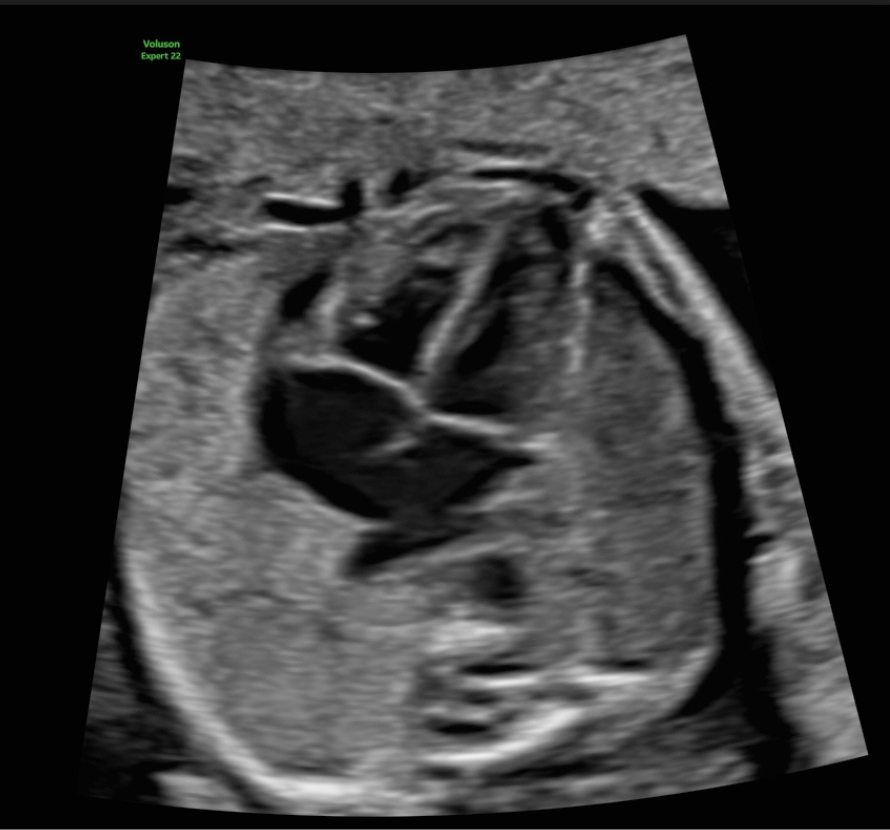

Echokardiographie

Fehlbildungen des Herz-Kreislaufsystems gehören zu den häufigsten Störungen des Neugeborenen und finden sich bei 0,5–1 % aller lebend geborenen Kinder.

Viele dieser Herzfehler sind nicht schwerwiegend und bedürfen keiner Therapie. Ein Teil jedoch kann gravierend, ja sogar lebensbedrohend bei der Geburt sein, sodass hier die Diagnose schon im Mutterleib lebensrettend sein kann. In diesen Fällen muss dann die Entbindung geplant in einem Zentrum mit den Neonatologen und Kinderkardiologen stattfinden, das Neugeborene benötigt bestimmte Medikamente oder muss intensivmedizinisch betreut werden. Manchmal sind auch sehr schnell Eingriffe und Operationen nötig.

Das Entdecken und die Beurteilung von fetalen Herzfehlern erfordert ein hohes Maß an Untersuchungserfahrung und eine entsprechende Geräteausstattung, sodass sie häufig im Rahmen von Routineuntersuchungen nicht erkannt werden. Daher sollten gerade Eltern mit einem erhöhten Risiko für fetale Herzfehler diese Untersuchung des kindlichen Herzens durchführen lassen.